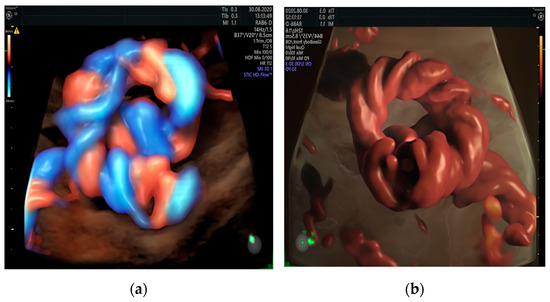

3.6. Umbilical Cord Cysts

3.7. Angiomyxoma/Hemangioma of the Umbilical Cord